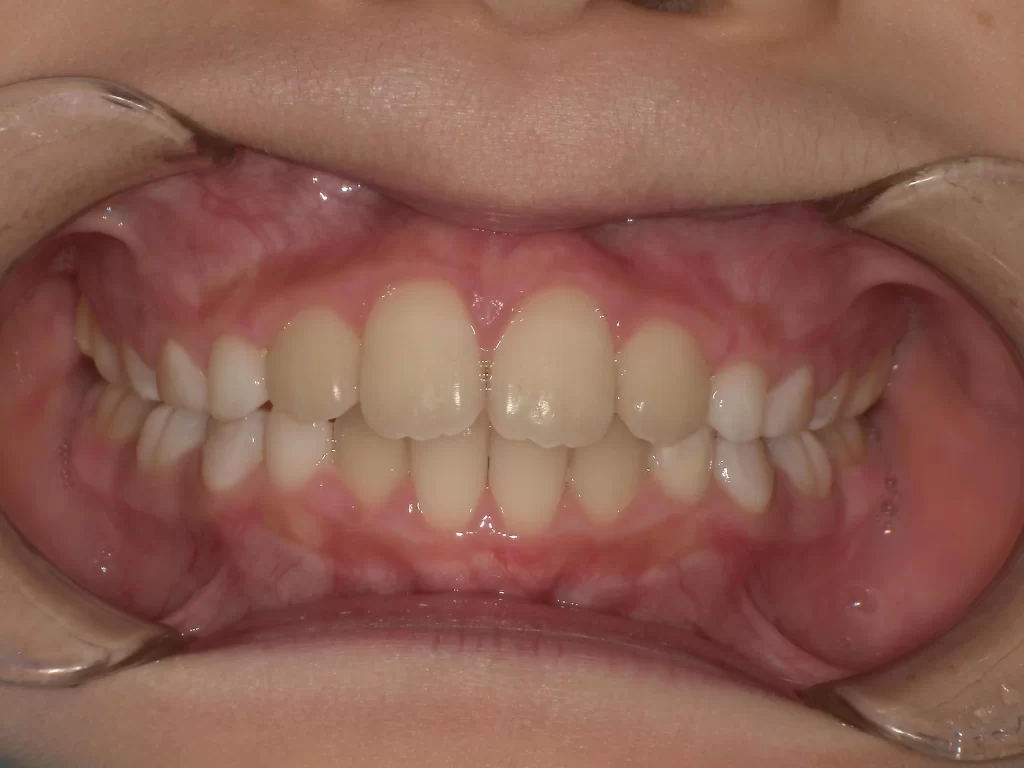

▼ 使用3ヶ月後(After)

- 年齢・症状: 10歳、叢生(ガタガタ)、過蓋咬合

- 治療法: プレオルソ

- 期間: 3ヶ月

- 結果: 装置を使うことで歯列の横幅が拡大し、ガタつきが自然に改善されました。深い噛み合わせも良くなっています。